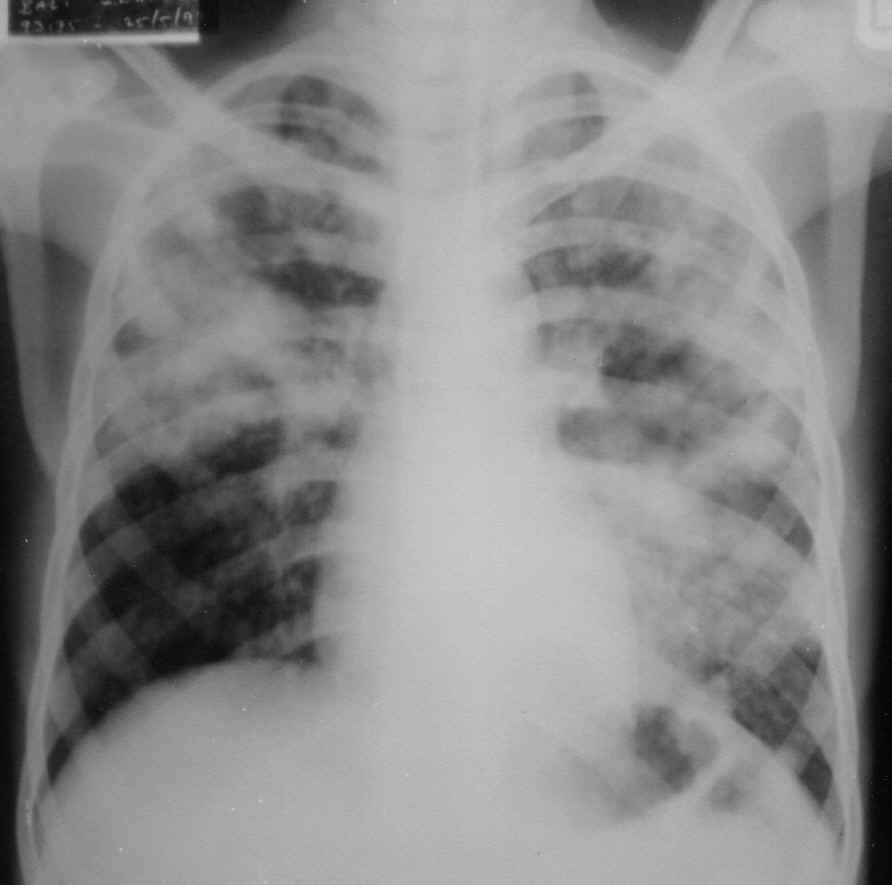

Causes of Impaired Gas Exchange

Acute head injury result from a trauma to the head leading to brain injury or bleeding within the brain, It's can make edema and hypoxia. Head injury cases is the